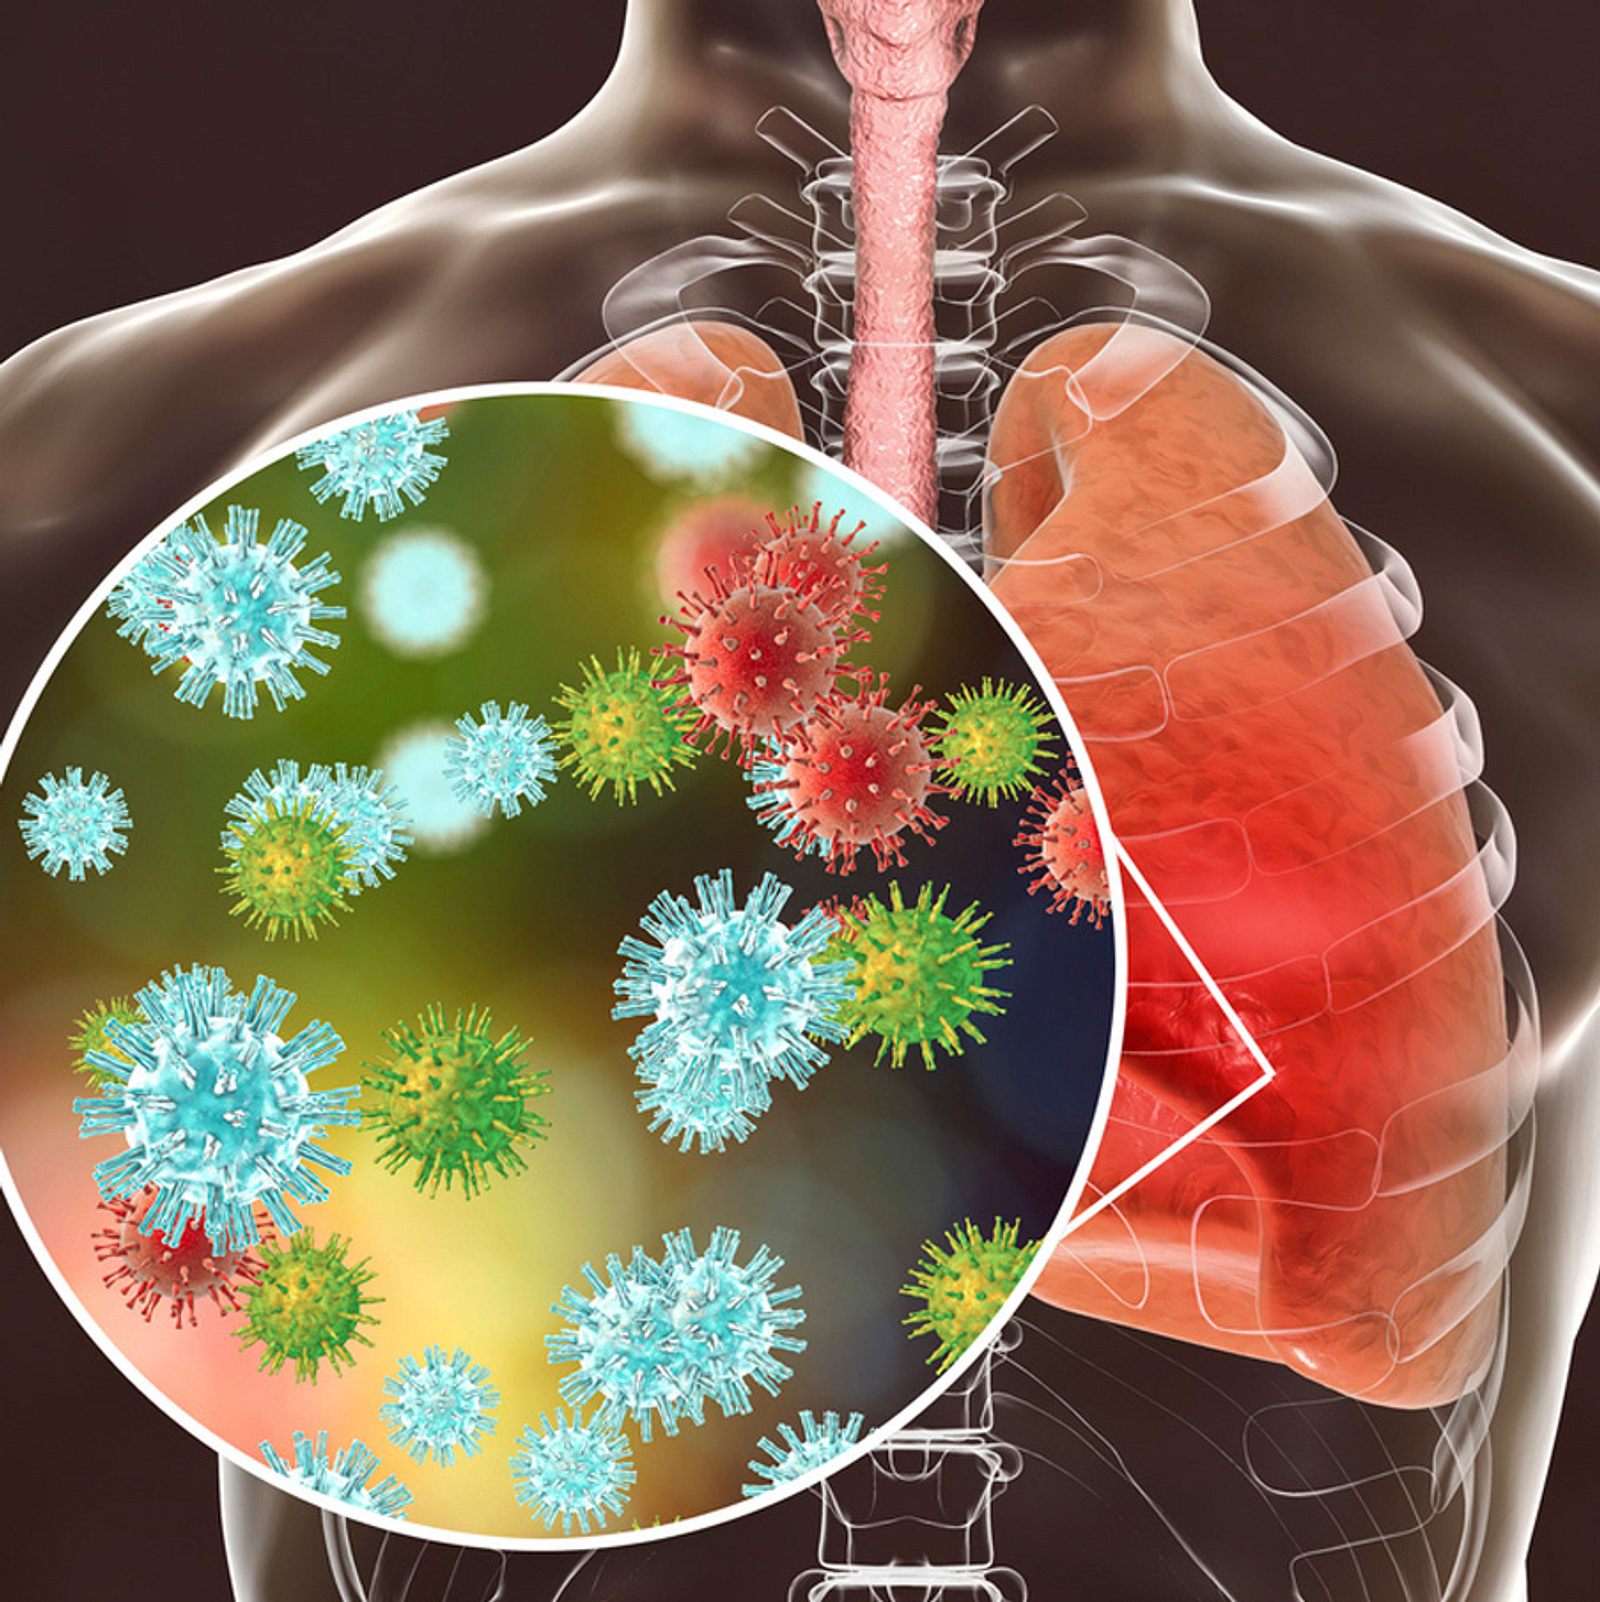

Фотографии бактерий, вызывающих бактериальные пневмонии у животных

Раздел: Другие животные